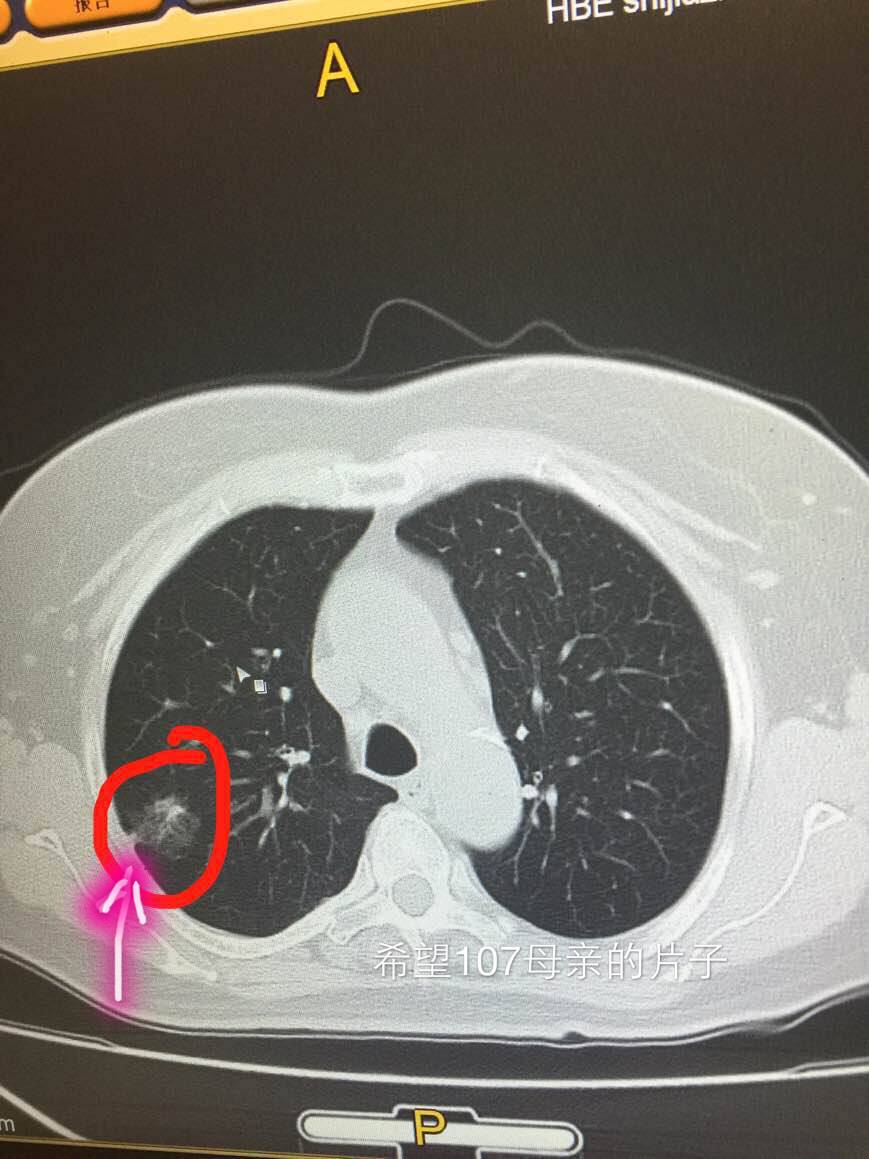

再看第二位患者,简称希望,大家看她的图跟第一位患者的几乎如出一辙,但陈医生第一次却只建议她定期复查

她们两位提供的病灶,都可以称为磨玻璃影,就像玻璃上被砂纸磨过,留下很粗糙的一片。

同时邻近胸膜的地方,都有点牵拉,就是胸膜局部有牵拉出一点。

大家仔细看一下两位的胸膜牵拉,月半弯的比较锐利,拉扯出来的部位呈三角形。而希望的片子里,拉扯出来的部位没那么锐利,绝呈一点不规则的方形。

而希望觅友的胸膜牵拉呢,则比较接近方形,最重要的是,没有症状,体检发现的。所以陈医生最初建议她定期复查。

但是,随着了解的深入,陈医生翻脸了,让她抓紧去手术。为什么呢?大家看看讨论截图就明白了。

几乎同样的病灶,希望觅友的主治医生比较犹豫,月半弯觅友的主治医生则比较果断。陈医生的建议也是直接积极切除比较放心,毕竟属于高危人群啊。